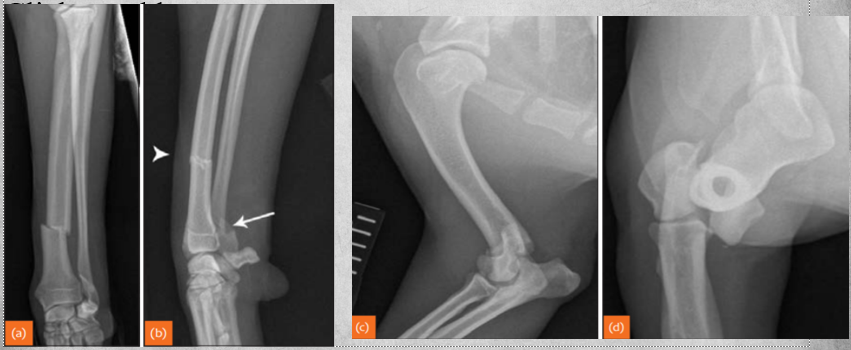

Describe Premature closure of growth plate.

e.g. distal ulna such as in image

results in growth discrepancy and may disrupt the function of the joint

What does this depict?

Premature closure of growth plate distal radius.